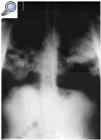

Fig. 1. Radiografía de tórax: estenso patrón alveolar bilateral con broncograma aéreo y zonas pseudoquísticas.